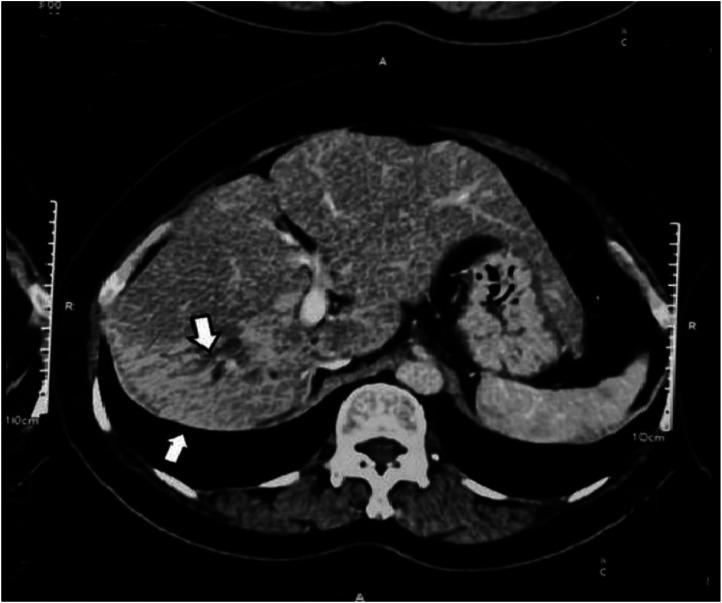

Hepatolithiasis is a rare condition requiring multidisciplinary treatment approach. In this case report we present a case of multiple hepatolithiasis successfully treated with right hepatectomy. A 54 years-old asymptomatic female with previous history of hepaticojejunostomy for recurrent CBD stone was diagnosed with hepatolithiasis during routine follow-up. Hepatolithiasis has multifactorial causation one of which is thought to be previous biliary surgery. This case report highlights the importance of routine ultrasound imaging during follow-up of the patient with history of previous biliary surgery for early detection of hepatolithiasis thus, mitigating further complications.

肝内胆管结石是一种需要多学科治疗方法的罕见病症。在本病例报告中,我们呈现了一例通过右半肝切除术成功治疗的多发性肝内胆管结石病例。一名54岁无症状女性,既往有因复发性胆总管结石行肝管空肠吻合术病史,在常规随访期间被诊断为肝内胆管结石。肝内胆管结石有多种病因,其中之一被认为是既往胆道手术。本病例报告强调了在有既往胆道手术史的患者随访期间进行常规超声检查对于早期发现肝内胆管结石的重要性,从而减轻进一步的并发症。